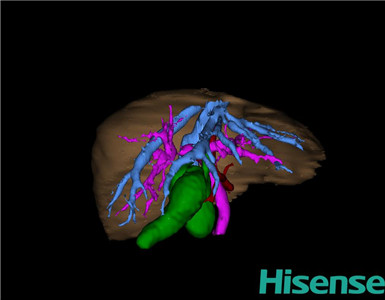

CT结果输入海信CAS系统后行3D重建及手术规划后,于2015-11-18全麻下行“胆总管囊肿切除+胆囊切除+胆总管-空肠吻合术”手术治疗:

将0.625mm双源薄层CT资料的静脉期和动脉期Dicom格式文件导入海信CAS系统。

通过调节窗宽窗位调整CT序号,对肝实质,胆囊,胆总管,下腔静脉,肝动脉、门静脉及肝静脉等进行三维重建;系统自动计算肝脏体积。

术前手术方案的规划。

完善术前准备后,选择右上腹纵口进入腹腔。结合海信CAS术前规划方案,探查见:胆总管4×2×2cm大小,胆囊约6×3×3cm,胆囊管迂曲,长约3cm。剥离、切除胆囊,游离胆总管,将之横断:①近端即肝总管,剪裁后备吻合用;②远端游离切除囊肿内壁,直至胆总管开口于十二指肠处,冲洗后予以结扎缝扎。距treits韧带20cm处直线切割吻合器横断空肠:①近端与其远端25cm处的空肠侧壁行端侧双层吻合,吻合口通畅;②远端断端封闭,其侧壁剪开,并经横结肠后提至肝门处,与剪裁的肝总管行端侧双层吻合。缝合修补胆囊床及系膜裂孔,肝门部放置橡胶引流管一根。温盐水冲洗腹腔。检查无活动性出血,清点纱布器械无误,依次缝合腹壁各层。术后胆囊标本家属过目,送检病理。手术时手术者可开启Hisense CAS系统手势控制功能,对胆囊周围血管、组织的解剖结构进行实时、全方观察、评估,起到术中导航作用。

术前三维重建:

重建图片